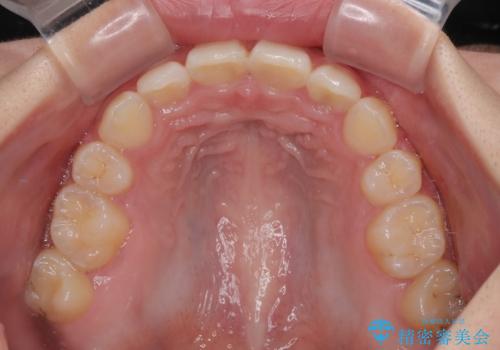

飛び出した前歯はしっかりと引っ込み、横顔の印象が大きく変化しました。

- 下唇の上に乗っかってしまうくらい前歯が飛び出していることを気にして来院された患者様です。

唇を閉じようとするとオトガイ部に力が入ってしまい、うまく閉じることができない状態であったため、上下左右の第一小臼歯4本を抜歯して、ワイヤー装置にて矯正治療を行うこととしました。